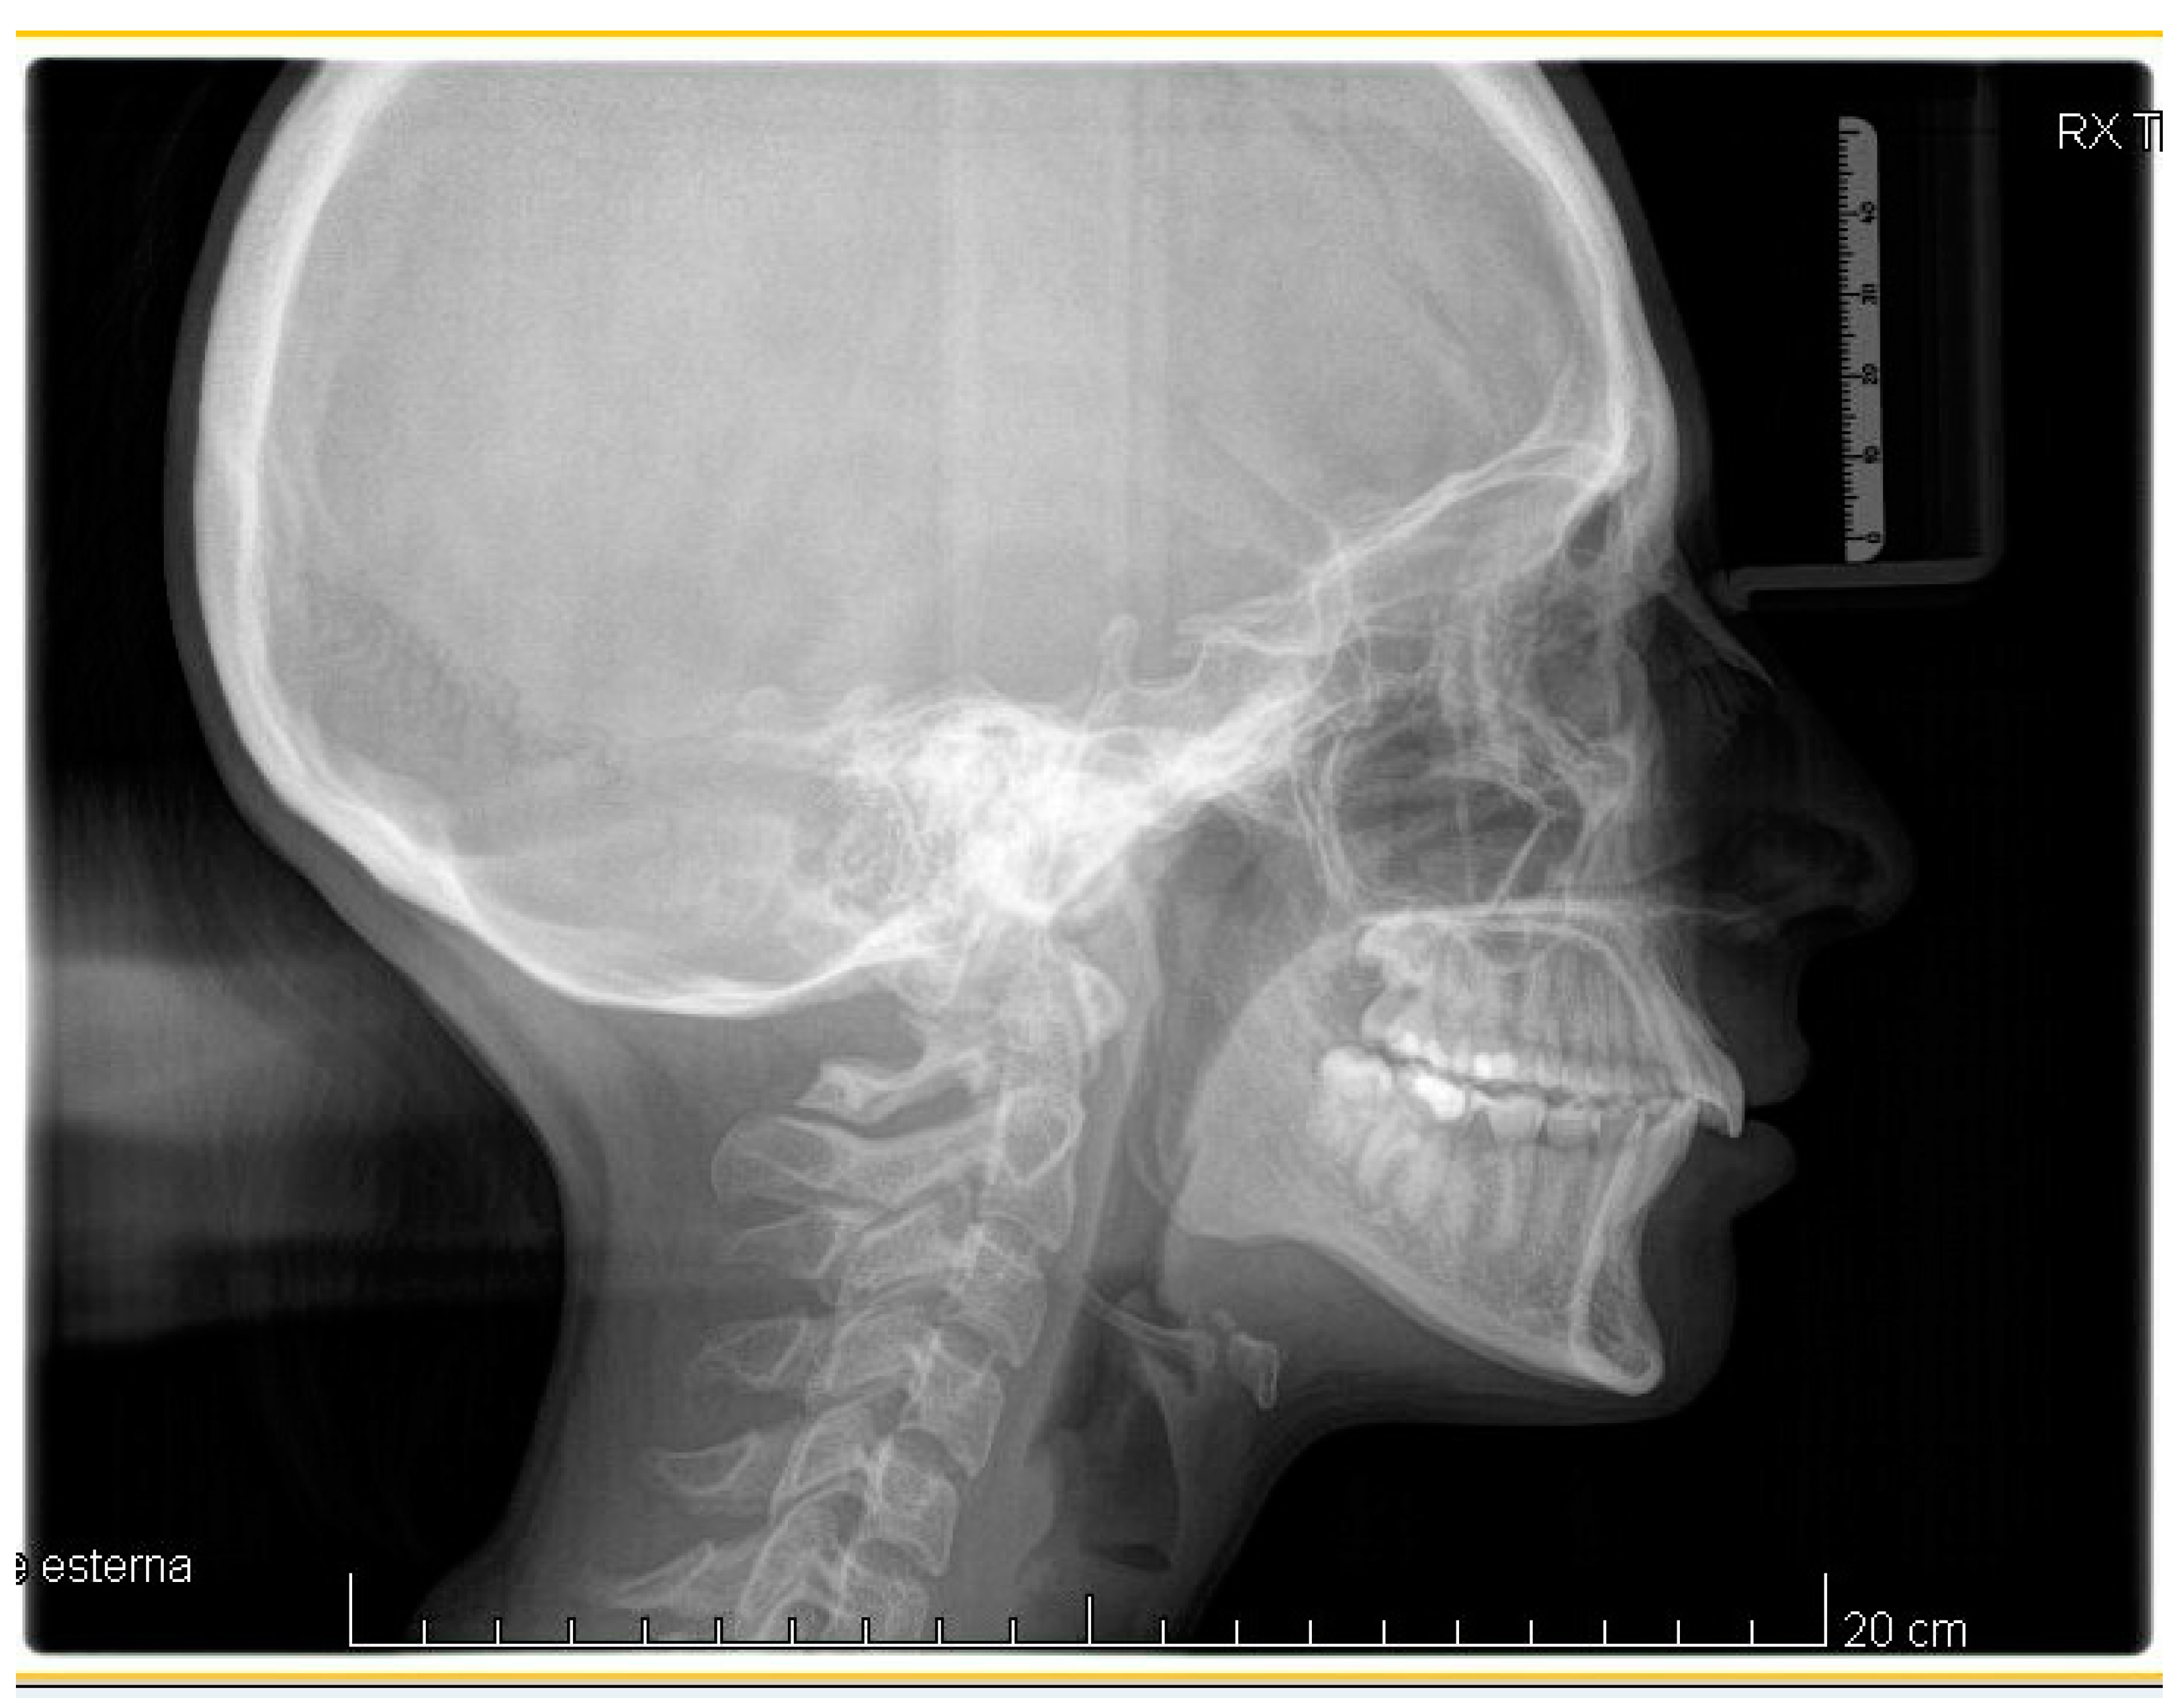

Figure 2.

Pre-treatment lateral teleradiography.

A case of CA therapy without attachments and without the aid of hybrid elements has been documented. The patient, an 18-year-old woman at the beginning of treatment (October 2021), signed written informed consent to orthodontic treatment and authorized the use of her anonymized treatment data, including photos, X-rays and virtual models of the dental arches. She needed to rehabilitate two edentulous areas corresponding to first maxillary and mandibular molars, both on the left side, assessed as irrecoverable for destructive caries at the time of the orthodontic evaluation (Figure 1). The patient refused rehabilitation with prosthetic implants and orthodontic treatments with fixed or hybrid fixed-removable therapy. Orthopanoramic (Figure 1) and lateral teleradiography of the skull (Figure 2) were acquired to make the necessary assessments. The cephalometric examination was performed using the Cephio© Cephalometric Analysis artificial intelligence driven platform (Cephio sp. z. o. o. [Ltd.]). Her skeletal class II malocclusion was due to maxillar and mandibular retrusion (SNA 80°, SNB° 74.6°, ANB 5.4°, SNPog 76.2°). She had “long face” (OP-SNP 21.1°), a posterior inclination of the jaw (MPGoGn- SNP 35.4°), slight hyperdivergence (FMA 26.2°), with pro-inclined lower incisors (1-NB 28.4°, IMPA 96.1°) and retroclined upper incisors (1-NA 14.1°, FMIA 57.7°). Overjet and overbite were severely altered (6 and 7 mm) (Table 3). Orthodontic treatment started 4 months after the first left maxillary and mandibular molar extractions. Intraoral and facial photos were captured (Canon© Coolpix A900, Canon, Tokyo 146-8501, Japan). Dentally, she had a first molar and canine class on the right side, and a first canine class on the left side in which the molar class was no longer assessable (initially it was a first class); however, a partial reduction in edentulous spaces was observed due to the movement of adjacent teeth (Figure 3) and lower incisors were moderately crowded. Precision silicone impressions (Elite HD+ Putty Soft Normal and Elite HD+ Super Light Body, Zhermack SpA, Badia, Italy) were taken using the double technique. Then, a virtual setup of the treatment with CAs was developed to evaluate its feasibility. It showed full closure of edentulous spaces and was also discussed successively with the patient. The orthodontist clarified there were no data from the literature (at that time) to support the successful movements required with only CAs. The orthodontist and patient started treatment by agreement. The informed consent to treatment was signed. It also covered clinical re-evaluation with solutions less favorable to the patient’s preferences if the results in the middle of treatment had been clinically unsatisfactory or unfavorable. The orthodontist explained the need to intercept any treatment complications to the patient. This also related to the predictability of intermediate results for medico-legal reasons, for the mutual protection of her as a patient and of the orthodontist as a professional responsible for the therapy. Initial and final virtual models were superimposed to evaluate the movements obtained (Maestro 3D©, AGE Solutions S.r.l., Pontedera- Pisa, Italy). At the end of the therapy, new X-rays were requested and new intraoral and extraoral photos were recorded.